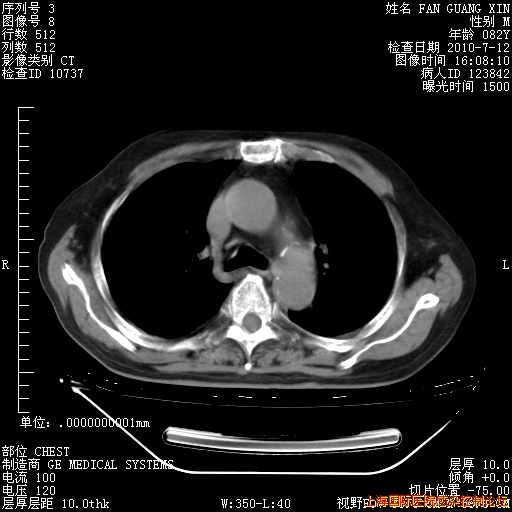

6月12日纵膈窗

6月10日改甲强龙80mg qd ,在南京年会期间体温不稳,18日有一次寒战后体温达39度。19日开始用甲强龙60mg bid ,加量后第二天就不发热。本打算在两周后即7月3日减量,但是7月2日洗澡受凉、发热、咳嗽、鼻音,口服复方大青叶片,甲强龙120mg用到9日(整整20天)。

自昨天起甲强龙改为80mg qd。

在抗结核治疗2周后一般情况逐渐好转。

整整相隔30天的肺部CT好像有所好转啊。甲强龙减量第3天,需要观察体温。

海管,自昨日你和我通完话后,不知您岳父消化道症状有无缓解?体温怎样?阅读7.12日胸部ct,个人认为目前激素治疗是有效的,甲强龙减量是适宜的。因在抗痨治疗,需密切观察肝功、肾功能和血常规。不过,老年、长期住院和大量使用激素,很担心菌群失调发生